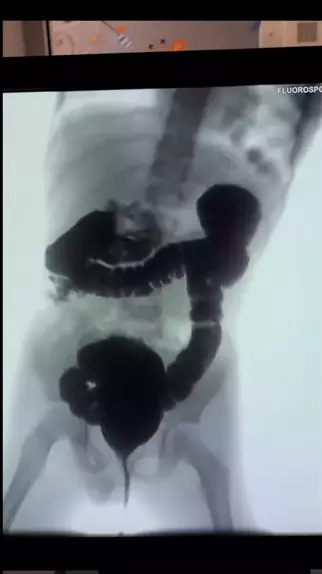

Megacólon é o termo usado para designar a dilatação e o alongamento do intestino grosso, fundamentalmente em razão de alterações da inervação dessa víscera. O megacólon pode ser congênito e adquirido. O megacólon adquirido é uma das principais manifestações da doença de Chagas e apresenta complicações como: Constipação crônica Distensão abdominal Fecaloma Volvo de sigmóide Colite isquêmica Úlceras (que podem ou não perfurar) #megacolon #anatomia #medical #medicine